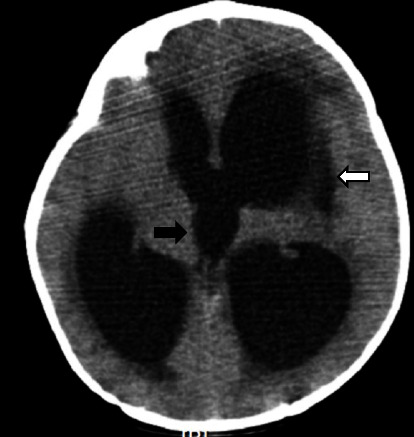

结核性脑膜炎(TBM)是一种严重的结核病,可导致很高的发病率和死亡率,尤其是在延误诊断和治疗的情况下。在本病例报告中,一名 9 个月大的女童因持续呕吐和局灶性抽搐入院。检查发现她右侧偏瘫。脑部影像学检查显示,她的脑膜呈强结节状强化、脑积水、左侧基底节低密度病变、动脉狭窄和血管炎以及陈旧性缺血性损伤。患者最初被诊断为急性缺血性中风,接受了阿司匹林和抗癫痫药物治疗。尽管进行了初步治疗,但患者的病情仍不见好转,于是进行了进一步诊断。结果发现了 TBM 诊断。该病例强调了将 TBM 视为神经系统症状的可能病因的重要性,尤其是在冠状病毒病 2019(COVID-19)大流行期间,严重急性呼吸系统综合征冠状病毒 2(SARS-CoV-2)感染和儿童多系统炎症综合征(MIS-C)的神经系统并发症病例中也可能出现类似症状。

Tuberculous meningitis (TBM) is a serious form of TB disease that can result in high morbidity and mortality, particularly if there are delays in diagnosis and treatment. In this case report, a 9-month-old girl was admitted with persistent vomiting and focal seizures. On examination, she was found to have a right-side hemiparesis. Brain imaging showed intense nodular leptomeningeal enhancement, hydrocephalus, a hypolucent lesion in the left basal ganglia, arterial stenosis and vasculitis, and an old ischemic insult. The patient was initially diagnosed with an acute ischemic stroke and was treated with aspirin and antiepileptic drugs. The patient's condition failed to improve despite initial treatment, leading to further diagnostic procedures. The results uncovered a diagnosis of TBM. The case highlights the importance of considering TBM as a possible cause of neurological symptoms, especially during the coronavirus disease 2019 (COVID-19) pandemic where similar symptoms can be present in cases of neurological complications of severe acute respiratory syndrome coronavirus 2 (SARS-CoV-2) infection and multisystem inflammatory syndrome in children (MIS-C).